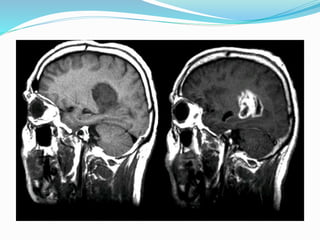

Indications for MR Imaging

 Diagnosis of Brain and Spinal cord diseases.

MRI Contrast Agent

 Gadolinium chelates are the commonly used MRI contrast

agenta and the next being Manganese. They are

paramagnetic elements with atomic number 64 with 7

unpaired electrons.

 It reduces the T1 relaxation time of protons and increases

the signal intensity on T1WI.

 Given as intravenous agents at dose of 0.1mg/k, they are

intravascular agents that improves the conspicuity of

lesions which further aids in confirming the diagnosis.

 Usually viewed in T1 weighted fat suppressed images in

multiplanar sections.

 Side Effects – Nausea Vomiting, Anaphylaxis and Seizures.

Uses of Gadolinium

 MR Arthrography.

 Enhancement of tumor masses and inflammatory

abscess.

 MR Urography.

 Contrast Enhanced MR Angiography.

 Dreaded complication of long term gadolinium use is

nephrogenic systemic fibrosis in patients with renal

failure and reduced GFR.